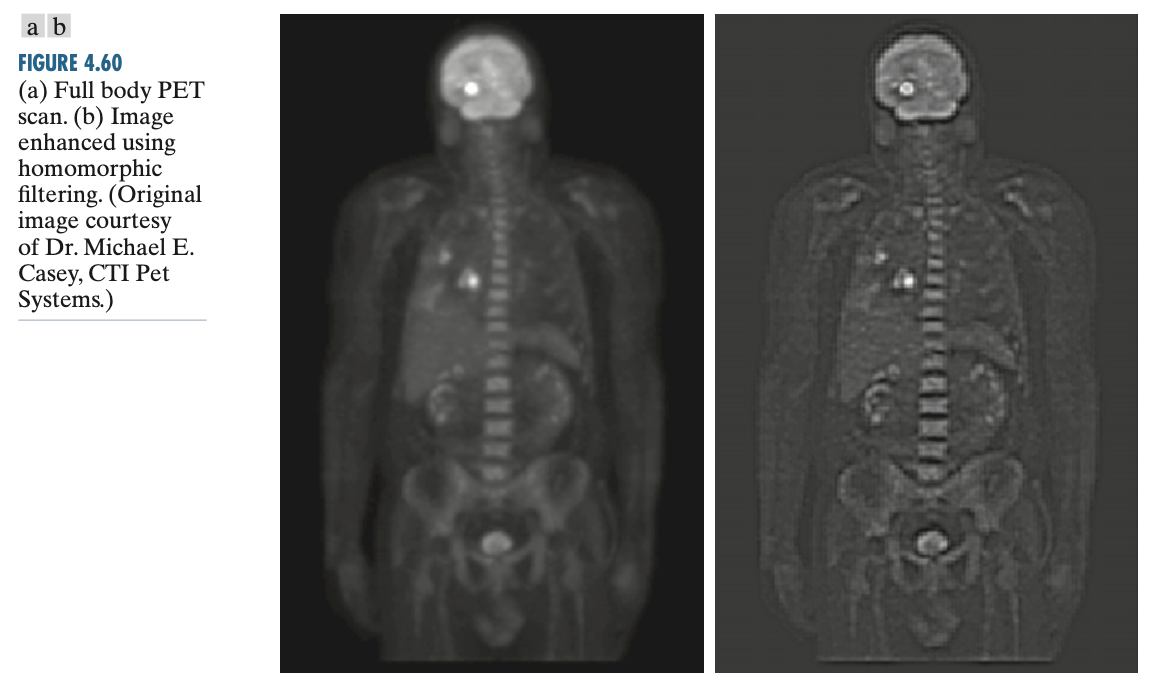

위 그림은 $\gamma_{\text{L}} = 0.25$ 그리고 $\gamma_{\text{H}} = 2$라고 가정한 필터입니다. 왼쪽 원본 영상에 비해서 오른쪽 필터링된 영상을 비교하면 상대적으로 엣지 정보(반사 정보)가 더 날카로워졌음을 관찰할 수 있습니다.